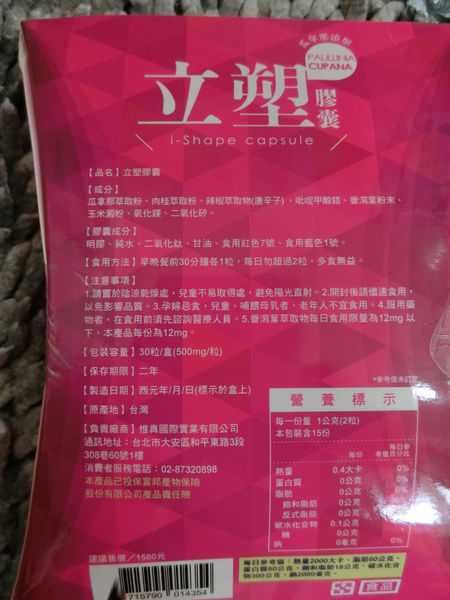

每一盒Supercut塑魔纖立塑膠囊都有三小包,每一小包有10顆膠囊

Supercut塑魔纖立塑膠囊的成分有:瓜拿那萃取粉、肉桂萃取粉、辣椒萃取物(唐辛子)、吡啶甲酸鉻、番瀉葉粉末、玉米澱粉、氧化鎂、二氧化矽。

之前上過相關課程,成分表是依照每項成分的多寡來排列順序,排在最前面的就是產品的主要成分!

那我就跟大家分享瓜拿那萃取粉、肉桂萃取粉和辣椒萃取物吧

瓜拿那萃取和辣椒萃取是可以幫助纖體瘦身常見的營養素!

1.「瓜拿那」是原產於亞馬遜流域的一種藤蔓植物,富含酵素可以幫助排便順暢,並且能抑制脂肪分解酵素,此外也有降低食慾的效果喔~~萃取物中含有天然咖啡因,可以提高新陳代謝率以及排出多餘水分!

2.「辣椒萃取物」則是可以幫助體內脂肪燃燒、增加卡路里的消耗,達到防止脂肪積聚的效果

3.「肉桂萃取物」看到肉桂,就想到麥當勞的蘋果派或是手掌麵包,雖然很多人很害怕那味道,但艾哥愛死肉桂了!!!!肉桂在古代被視為是最有價值的東方香料之ㄧ,中世紀時,肉桂的聲望僅次於昂貴的黑胡椒,除了香料和薰香價值, 傳統上肉也被用來治療消化不良、脹氣、關節疼痛、出血和經痛,研究也指出肉桂可以促進新陳代謝喔

食用方式:早晚餐前30分鐘各1粒,每日不超過2粒。(多食無益)

包裝是桃紅色的

番瀉葉萃取物每日食用限量為12mg以下,